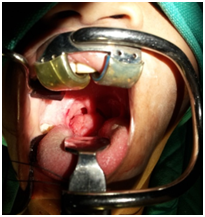

Figure 1 Preoperative picture of the patient showing base of tongue mass.

A 14 year old male presented with complaints of dysphagia for one year. On examination, a pinkish irregular growth approximately 3.5cm in transverse diameter was seen in right side of base of tongue. It was immobile, nontender, firm, and non compressible swelling which was blanching on pressure. Rest of the ENT examination was normal. A MRI scan was done and suggestive of mass epicentered in posterior 1/3 of tongue mainly on right side, crossing mid line with size of 20 X 29 X 34mm and infiltrating the intrinsic muscles of the tongue. It was heterogeneously hypointense on T1W1 and heterogeneously hyperintense in T2W1 images. Delayed post contrast enhancement was noted and provisional diagnosis of Haemangiolymphangioma was given. The patient was given empirical treatment with oral propanolol and local sclerosant (phenol) injection. However, there was no decrease in size of the mass and decision was taken for surgical excision. The patient was taken up for coblation assisted surgery under general anaesthesia. The upfront tracheostomy was offered to secure the airway and to avoid any postoperative complications after obtaining informed consent.

During tracheostomy, incidentally an unusually high Innominate artery was encountered over trachea in midline traversing laterally to the right side of the neck at the level of third tracheal ring. Through per oral approach the tongue mass was lifted from the underlying muscles in a plane using coblation and bipolar cautery and was excised in to with a margin of 5mm all around including at depth. Post operative period was uneventful. The patient was decannulated on day two and the oral feeds were started on day two only. The patient was discharged on post operative day three.